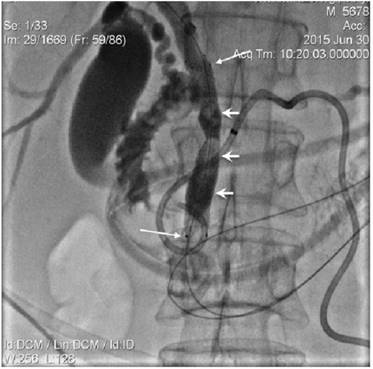

Figure 3

Endoluminal 8 Fr diameter RF catherter (long arrows) was positioned in biliary duct obstructed segment over the wire. External-internal PD drain was identified by short arrows.